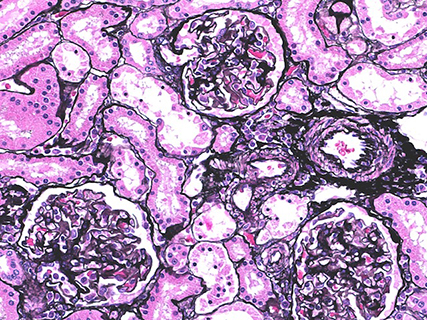

PAM染色(マーモセット腎臓)